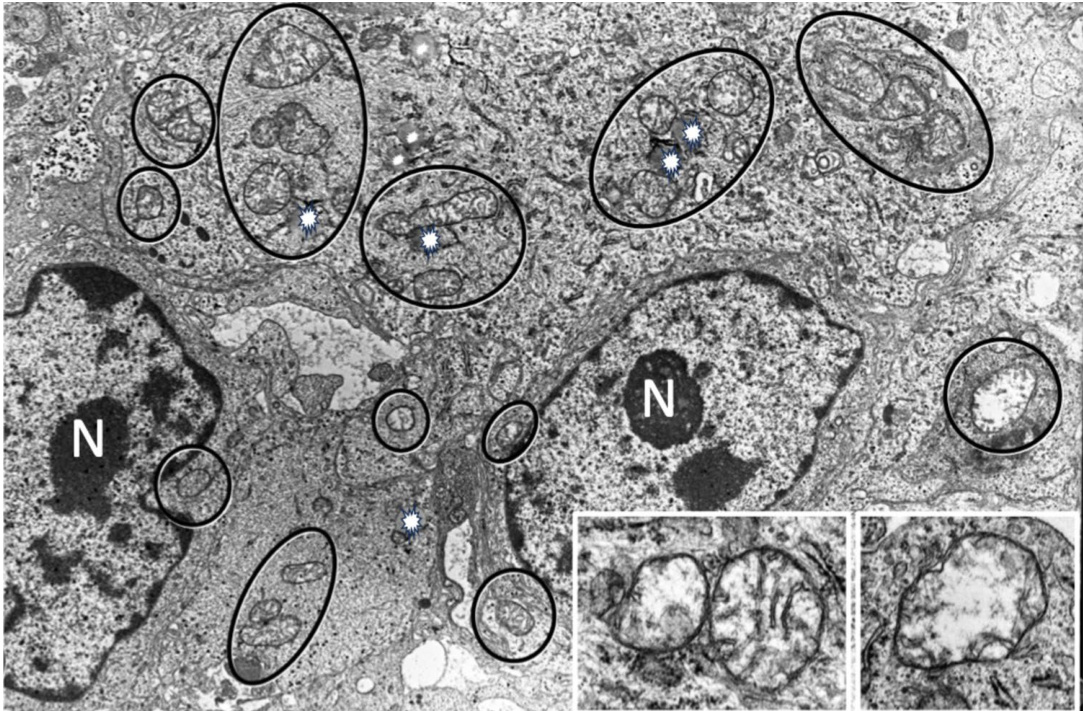

Fig. 2 Abnormal mitochondria and lipid droplets in glioblastoma. Transmission electron microscopy (TEM) image of human glioblastoma tumor biopsy showing cells with numerous mitochondria with total-subtotal cristo lysis and dysmorphic cristae (indicated by circles and ellipses). The presence of lipid droplets (indicated by white asterisks) is apparent and abundant. N indicates the nucleus. Magnification is at $4000\times$ and insert micrographs at $8000\mathrm{x}$ . (Adapted from J Electron (Tokyo). 2008; 57:33–39)

图 2: 胶质母细胞瘤中的异常线粒体和脂滴。人类胶质母细胞瘤活检样本的透射电子显微镜 (TEM) 图像显示,细胞中存在大量线粒体,这些线粒体呈现完全或部分嵴溶解及形态异常 (由圆形和椭圆形标示)。脂滴 (由白色星号标示) 明显且大量存在。N 表示细胞核。放大倍数为 $4000\times$,插图为 $8000\mathrm{x}$ 倍放大。(改编自 J Electron (Tokyo). 2008; 57:33–39)